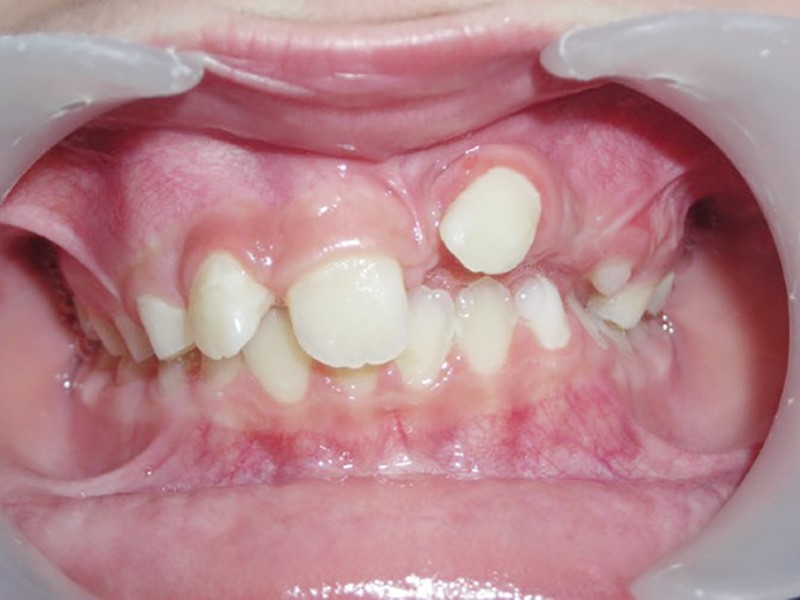

La 22 doit être remise sur l’arcade et le choix est fait de la mettre en lieu de 21 (fig. 4), puis de la maquiller pour temporiser en attendant l’évolution des autres dents définitives, et éviter le port d’une prothèse amovible transitoire (P.A.T.) tout en ramenant de l’os alvéolaire dans l’espace de 21.

L’interception dure 6 mois, et les attaches antérieures sont laissées en place et ligaturées (fig. 5) pour permettre une contention légère. On note la perte de la médiane.